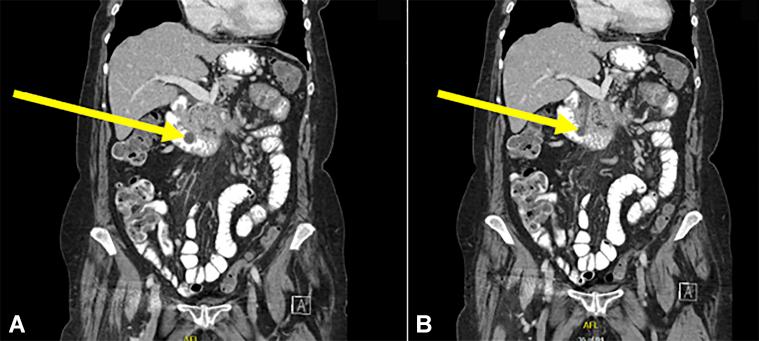

Abou Saleh Mohannad, Vozzo Catherine, Chahal Prabhleen

Department of Gastroenterology and Hepatology, Cleveland Clinic Foundation, Cleveland, Ohio.

VideoGIE. 2020 Dec 10;6(2):98-100. doi: 10.1016/j.vgie.2020.10.015. eCollection 2021 Feb.